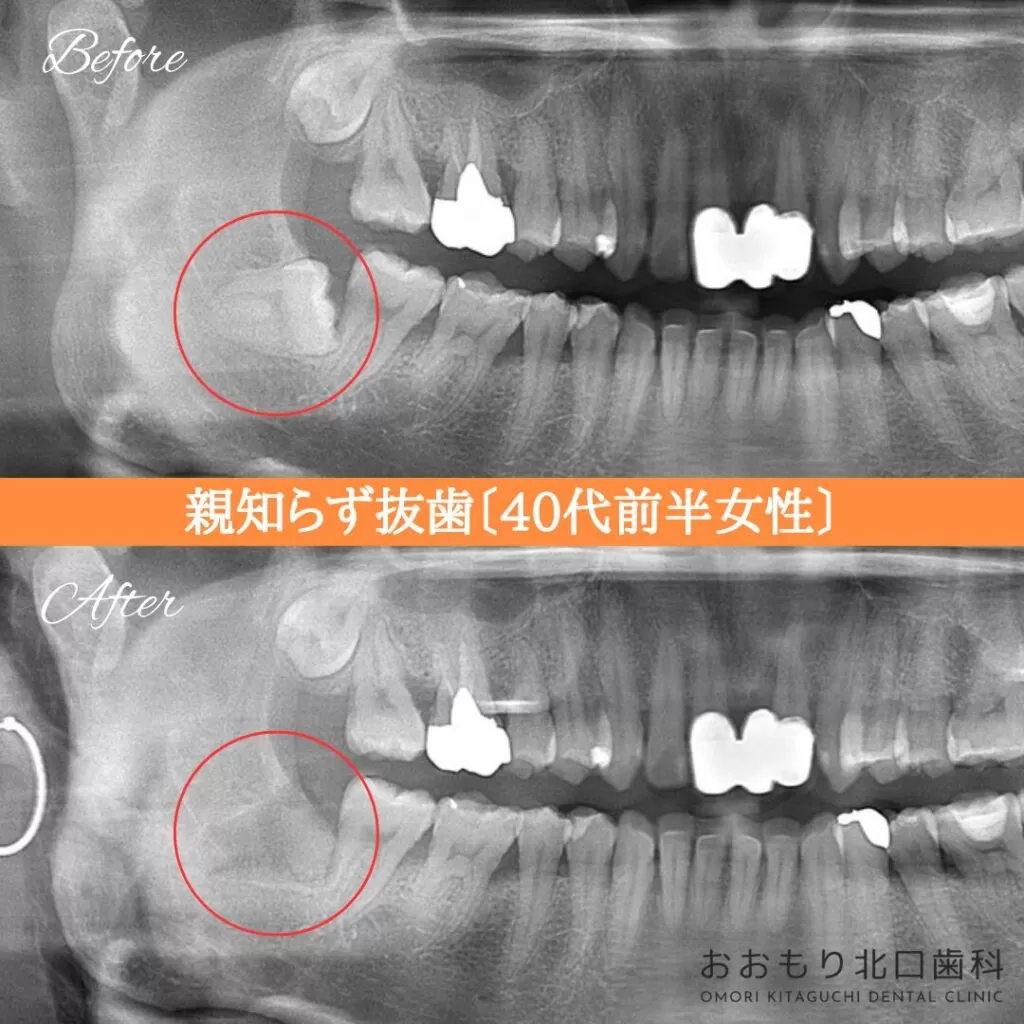

症例紹介⑦親知らず抜歯(40代前半女性)

本日は「親知らず抜歯」を行われた患者さまのビフォーアフターをご紹介します。

【治療名】右下親知らず抜歯

【施術者】 Dr菊池